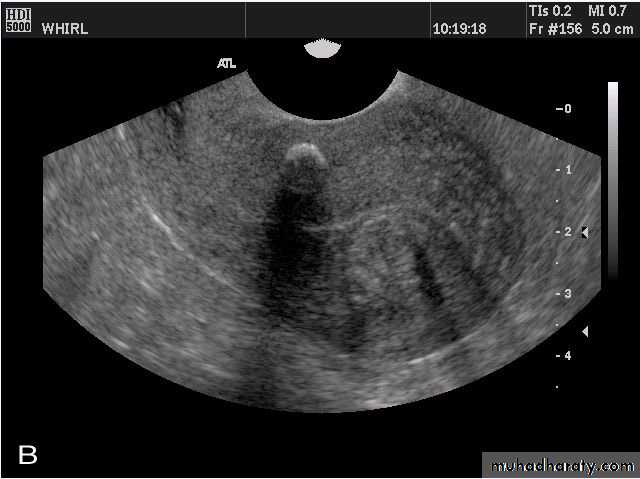

Ovarian hyperstimulation syndrome (OHSS):

This young adult female patient was examined to evaluate the uterus and ovaries. She was under treatment for infertility and was using gonadotropins. Ultrasound images of the ovaries show grossly enlarged ovaries with large cysts (measuring 2.6 to 3 cms.) in both ovaries. These ultrasound findings are diagnostic of OHSS or ovarian hyperstimulation syndrome.

• Ovarian hyperstimulation syndrome (OHSS):

The ultrasound image again show hyperstimulated ovaries. Both ovaries are grossly enlarged and cystic.